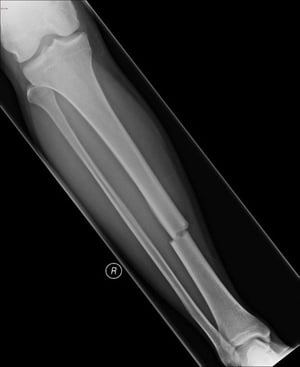

경골축의 횡방향 골절

이 횡방향 골절은 경골의 중축에 영향을 미칩니다.

이미지 제공: Danielle Campagne, MD.